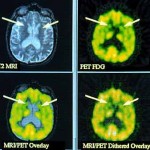

HD es un trastorno hereditario causado por una mutación en el gen de una proteína llamada huntingtina. Los depósitos de la proteína anormal se acumulan en el cerebro, causando la destrucción de las células cerebrales.Los síntomas de la HD por lo general aparecen por primera vez en la mediana edad y empeora con la 10 – a 30 años de evolución del trastorno, lo que lleva a la muerte de una variedad de complicaciones. SIRT1 es un importante regulador de la actividad de las proteínas implicadas en muchas funciones críticas – incluyendo el metabolismo energético, la inflamación y la tolerancia al estrés – y los estudios recientes han sugerido que protege contra los efectos de varias enfermedades neurodegenerativas.

En experimentos con un modelo de ratón de alta definición, los investigadores mostraron por primera vez que la anulación de Sirt1 expresión en el cerebro acelera la aparición de HD-como patología – tales como los agregados de huntingtina mutante y el daño celular aumenta en las áreas clave del cerebro. Por el contrario, una cepa de ratones de alta definición en la que se sobreexpresa Sirt1 vivido más tiempo, con la neurodegeneración significativamente menor y la agregación de huntingtina, que los ratones de alta definición en la que Sirt1 expresión no se alteró. Experimentos celulares demostraron que la sobreexpresión de Sirt1 directamente protege a las neuronas del efecto tóxico de la huntingtina mutante.